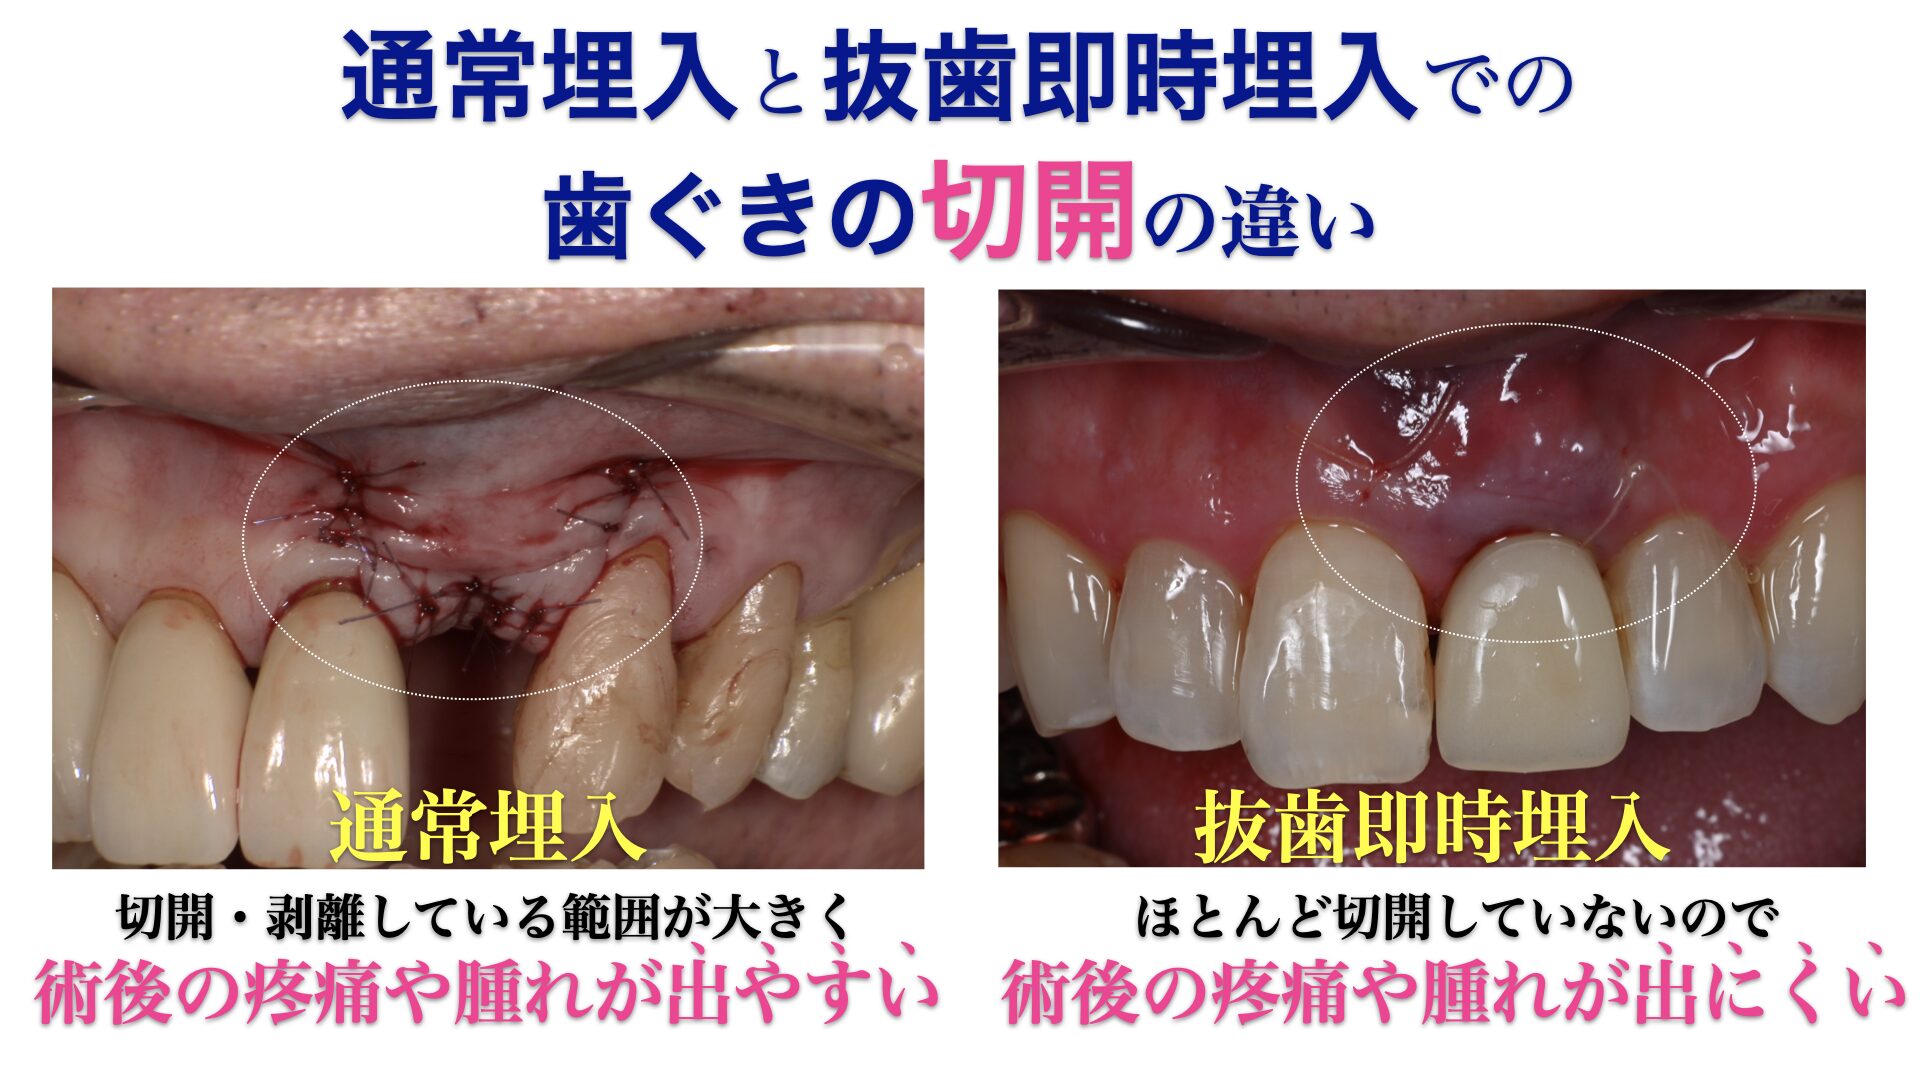

歯周外科治療Periodontal surgery

基本的な歯周病治療のほか、歯周組織を再生する治療や、歯肉の移植なども行います。認知症をはじめとする、全身疾患の要因にもなる歯周病を原因から改善します。